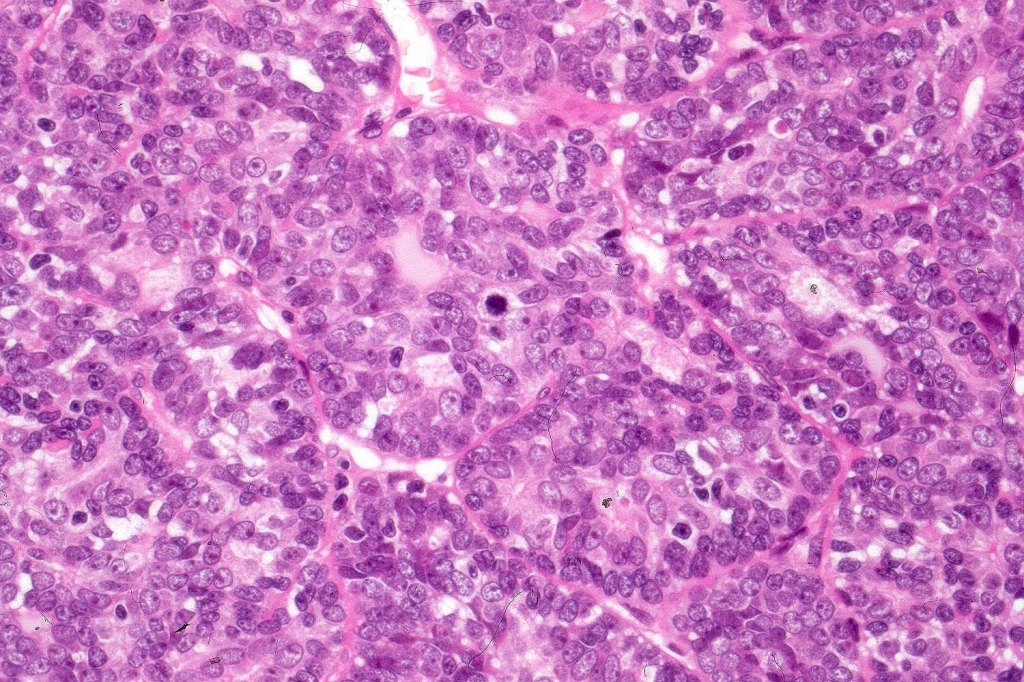

Histological features

•Malignant component shows loss of dual cell population, increased mitotic activity, atypical mitoses & necrosis

•Perineural infiltration & LVI may be present

•Diagnosis depends on H/E rather than IHC

•The alternative classification into low grade (with only mild atypia and increased mitotic activity) and high grade variants has some merit although in any individual case this can be hard to apply unless the whole tumor has been sampled and is of uncertain biological merit.